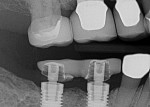

Records from her local surgeon and dentist were requested. Radiographic review (Figure 2) and emails from her regular dentist prompted concern about a lack of adequate interocclusal space for final restorations. Due to limited space, screw-retained hybrid abutment/crowns were planned.

The treatment began with taking preoperative photographs and performing a clinical examination. Following removal of the lower right provisional and placement of the ScanPosts (Dentsply Sirona, sironausa.com) and ScanBodies (Dentsply Sirona) (Figure 7), a digital impression was taken of each arch and a buccal bite registration. During the CEREC™ (Dentsply Sirona) computer-aided design process, the team realized insufficient interocclusal space existed to create hybrid abutment crowns (Figure 8) at the current OVD. Removal of porcelain from the opposing arch was not an option. The decision was made to gain space by increasing the OVD, employing the revised treatment plan. The implant-supported provisional was then hand torqued back onto implant Nos. 30 and 31 to prevent tissue collapse during treatment.